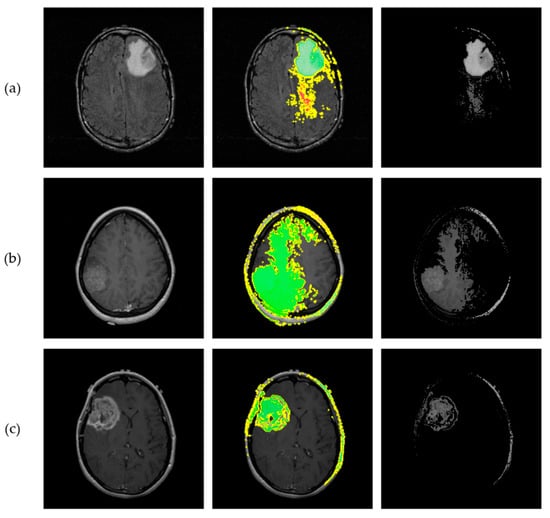

3.5. Explainable AI Insights

2.5. Explainable AI Methods